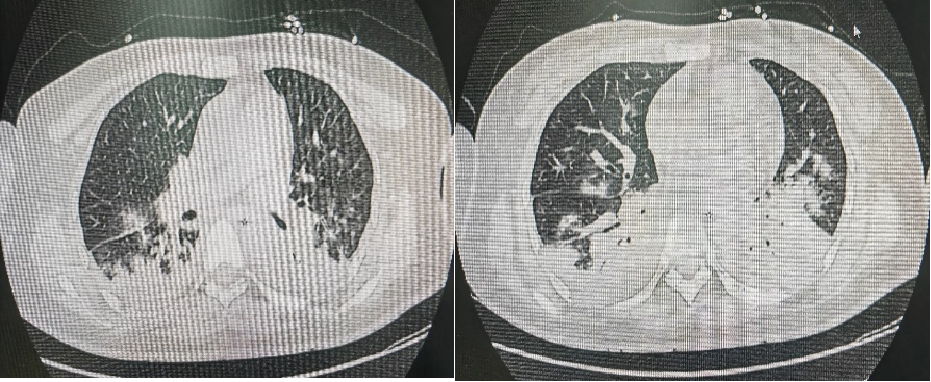

常见的 CT 表现:双肺下叶或者单侧,主要靠近背侧以及脊柱旁的斑片影或实变影,后者密度比较高,在其内常存在充气支气管征,部分由于支气管腔存在阻塞性疾病进而使产生的肺内气体减少,或者是完全无气而导致下肺体积变小现象,且内缘边界模糊,患侧绝大部分会伴有轻度胸膜反应或少量至中量胸水(如图 1)。

图片图 1. 王某,44 岁女性,因小脑血管母细胞瘤切除术后 12 年,发现复发 1 月余,行左侧卧位电生理监测经乙状窦后入路脑干复发血管母细胞瘤切除术,术后发生坠积性肺炎。(来源:作者提供)